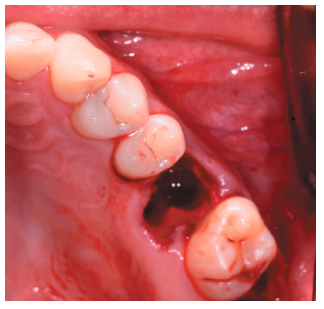

Caso clínico: se presenta el caso de un varón de 28 años, que acudió a consulta por la presencia de unos restos radiculares en localización de primer molar superior izquierdo. Se realizó un autotrasplante dental, siendo el diente donante el tercer molar superior izquierdo, que se trasplantó al alveolo del primer molar, mostrando buena evolución clínica y radiográfi ca.

Clinical case: a clinical case of a 28-yearold man is presented, who went to dental clinic for removal of left fi rst molar roots. An autotransplant was performed using left third molar as donor tooth, which was transplanted into fi rst molar alveolus, showing promising clinical and radiographic evolution.